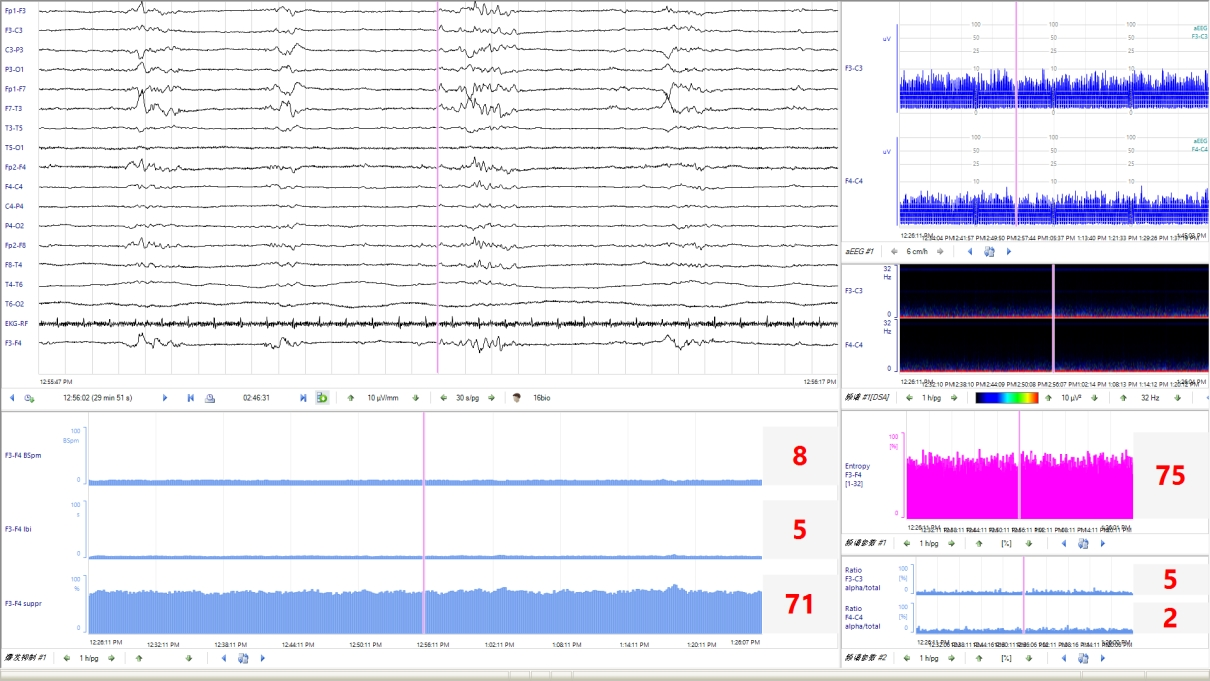

Q3:新生兒 aEEG的評價標準是什么?aEEG 主要從背景活動、睡眠周期及驚厥三方面進行評價和分類。aEEG的連續(xù)性亦被臨床廣泛關(guān)注。

睡眠周期未達到相應(yīng)PMA成熟度的表現(xiàn),則為睡眠周期落后于胎齡。3、驚厥發(fā)作(1) 單次發(fā)作:aEEG波譜帶短暫中斷,呈“駝峰”、“城垛”、“拱形”、“缺口”樣改變。(2) 反復(fù)發(fā)作:aEEG出現(xiàn)多次上述改變。(3) 驚持續(xù)狀態(tài):既往認為發(fā)作時間超過30min或腦電圖監(jiān)測過程中異常放電占總監(jiān)測時間的50%以上為驚持續(xù)狀態(tài)。然而,為了減少驚厥發(fā)作時間及可能造成的神經(jīng)損傷,aEEG表現(xiàn)為“鋸齒”樣波形時,即可根據(jù)不同的發(fā)作形式,在更短的時間窗內(nèi)做出臨床治療決策。在KCNQ2基因致病性變異所致的發(fā)育及癲癇性腦病中,發(fā)作期aEEG呈現(xiàn)短暫上升后急劇下降(倒駝峰狀)表現(xiàn),aEEG中的短暫上升圖形對應(yīng)原始腦電圖的發(fā)作期圖形,急劇下降圖形對應(yīng)原始腦電圖發(fā)作期后的廣泛性電壓衰減、甚至抑制圖形。4、總體評估綜上,近足月兒和足月兒可綜合aEEG的背景活動、睡眠周期及有無驚厥進行總體評估,分為正常、輕度異常和重度異常,aEEG異常提示患兒可能存在腦損傷或腦發(fā)育成熟度延遲。Q4:早產(chǎn)兒 aEEG的特點及其臨床意義?早產(chǎn)兒aEEG的背景活動、睡眠周期隨胎齡而變化。隨胎齡的增加,振幅上邊界逐漸降低,下邊界逐漸升高;睡眠周期也從最早的無法辨認到出現(xiàn)成熟的正弦樣變化;aEEG圖形由不連續(xù)圖形過渡為連續(xù)圖形。見表1。通過aEEG圖形變化可定性評價早產(chǎn)兒的腦發(fā)育情況。

Q5:aEEG診斷新生兒腦病及判斷神經(jīng)發(fā)育預(yù)后的價值?aEEG可用于輔助診斷出生后6h內(nèi)缺氧缺血性腦病(hypoxic-ischemic encephalopathy,HIE)的嚴重程度。窒息新生兒出生后6h內(nèi)aEEG背景活動異常可作為開始亞低溫治療的準入標準,建議至少監(jiān)測30min。但是不能因aEEG背景活動正常將HIE新生兒排除在亞低溫治療之外,需進一步結(jié)合臨床。建議在新生兒HIE亞低溫治療和復(fù)溫期間進行連續(xù)aEEG監(jiān)測,或者每天監(jiān)測一次、每次至少2h,以評價腦功能和疾病轉(zhuǎn)歸。aEEG對預(yù)測HIE新生兒預(yù)后具有一定的敏感性和特異性,應(yīng)重點關(guān)注aEEG背景活動及其動態(tài)變化趨勢。行亞低溫治療的患兒,48h aEEG的背景活動和睡眠周期很關(guān)鍵,治療48h后aEEG正常的患兒預(yù)后好。復(fù)溫時無睡眠周期與預(yù)后不良相關(guān)未行/無條件行亞低溫治療的患兒,6h aEEG正常的患兒神經(jīng)發(fā)育預(yù)后好;36h有睡眠周期的患兒神經(jīng)發(fā)育預(yù)后好。持續(xù)的背景活動異常和缺乏睡眠周期與2歲時發(fā)育遲滯相關(guān)。代謝性腦病患兒中,70% aEEG背景活動異常,60%出現(xiàn)癲癇發(fā)作。Q6:如何應(yīng)用aEEG篩查和準確識別新生兒驚厥?新生兒驚厥的臨床表現(xiàn)不典型,部分驚厥可只有電發(fā)作而無臨床表現(xiàn),故可能因漏診而延誤治療,從而引起或加重腦損傷。另外,部分抗驚厥發(fā)作藥物有潛在的神經(jīng)毒性。故通過持續(xù)的床旁腦電監(jiān)測,可以減少漏診、避免過度診斷,并指導(dǎo)抗驚厥發(fā)作藥物的精準使用。aEEG對驚厥監(jiān)測的優(yōu)點是時效性強,可以直接、快速地在床旁開展,且可長時間監(jiān)測,常用于新生兒驚厥的篩查、療效監(jiān)測和評估。但由于aEEG為時間壓縮圖形,可能會漏掉振幅低、發(fā)作時間短(<30s)和起始部位距離監(jiān)測電極遠的驚厥。缺乏發(fā)作期腦電圖的時空演變圖形(通常在多通道腦電圖中可以看到)是aEEG的另一個重要限制,如結(jié)合有視頻記錄的原始腦電圖,aEEG對于驚判讀的敏感度和特異度可分別達到76%和85%左右。早產(chǎn)兒驚厥的診斷在臨床上更為棘手,由于早產(chǎn)兒驚厥時臨床癥狀相對不明顯或不典型,發(fā)作期腦電活動持續(xù)時間相對短,振幅低,擴散范圍小,發(fā)作期的aEEG圖形常不易識別;新生兒重癥監(jiān)護室中呼吸機的使用和各類操作干擾也可造成疑似驚厥發(fā)作圖形而誤診。因此aEEG中出現(xiàn)任何可疑的上下邊界短暫改變時,均需通過對比同期的原始腦電圖加以證實。視頻腦電圖(video-electrencephalography,VEEG)是新生兒驚厥診斷的金標準。沒有多導(dǎo)VEEG的前提下,aEEG可以用于新生兒驚厥發(fā)作的監(jiān)測,但是需要同時分析原始腦電圖,最大限度避免偽差干擾導(dǎo)致的誤診。當臨床高度懷疑有驚厥發(fā)作而aEEG未監(jiān)測到癇性放電時,建議增加導(dǎo)聯(lián)數(shù)量,使用8導(dǎo)以上帶有視頻監(jiān)測的aEEG設(shè)備。有條件的醫(yī)院應(yīng)進行長程vEEG監(jiān)測。使用aEEG進行新生兒驚厥診斷時,建議至少有一次vEEG檢查,并與神經(jīng)電生理專家密切合作。